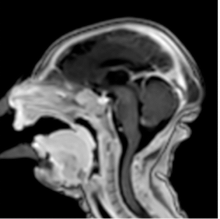

2. MRIs During Pregnancy Are Safe, But Gadolinium Scans May Increase Risk to Fetus